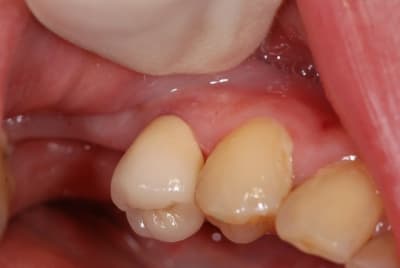

Regardez ce que je viens de recevoir de mon prothésiste habituel.

Vous conviendrez que le résultat n'est pas terrible, mais est assez représentatif de ce que je reçois.

A chaque fois, je met en cause mes piètres talents de prise de teinte, mais vous constaterez sur la deuxième photo que j'étais quand même plus proche que lui.

Le teintier que je présente est un A3,5.

c'est une ccm monocouche avec un peu de maquillage au collet ,maqquillage qui finira par s'en aller..

trop globuleuse et epaisse (maisquelle epaaisseur lui as tu laissé?)

et pas très bien sculptée(mais qu'y a t'il en face?)

Pour ceux qui émettaient l'hypothèse du manque de place pour le prothésiste, je n'ai pas de photo en occlusion, mais vous pourrez constater qu'au moins en périphérique il avait largement la place. Et je vous demande de bien vouloir me croire pour la place en occlusal.